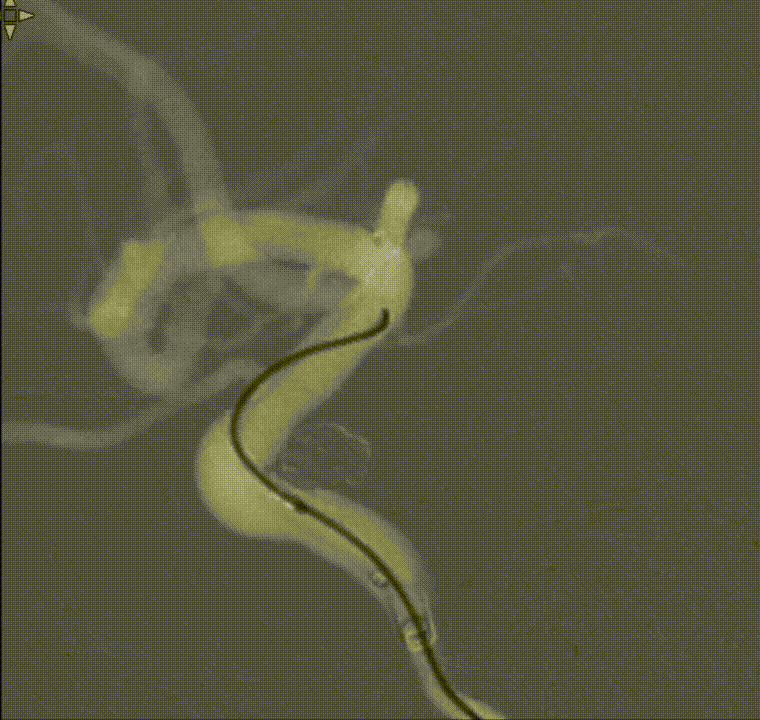

工作位正位造影(图片)

工作位侧位造影(图片)

工作位正位造影(视频)

工作位侧位造影(视频)

璞慧 0.017微导管塑形

Asahi 0.014微导丝塑形后辅助Echelon 10微导管进入A2远端备支架释放。

Asahi 0.014微导丝导引璞慧 0.017微导管进入动脉瘤内。